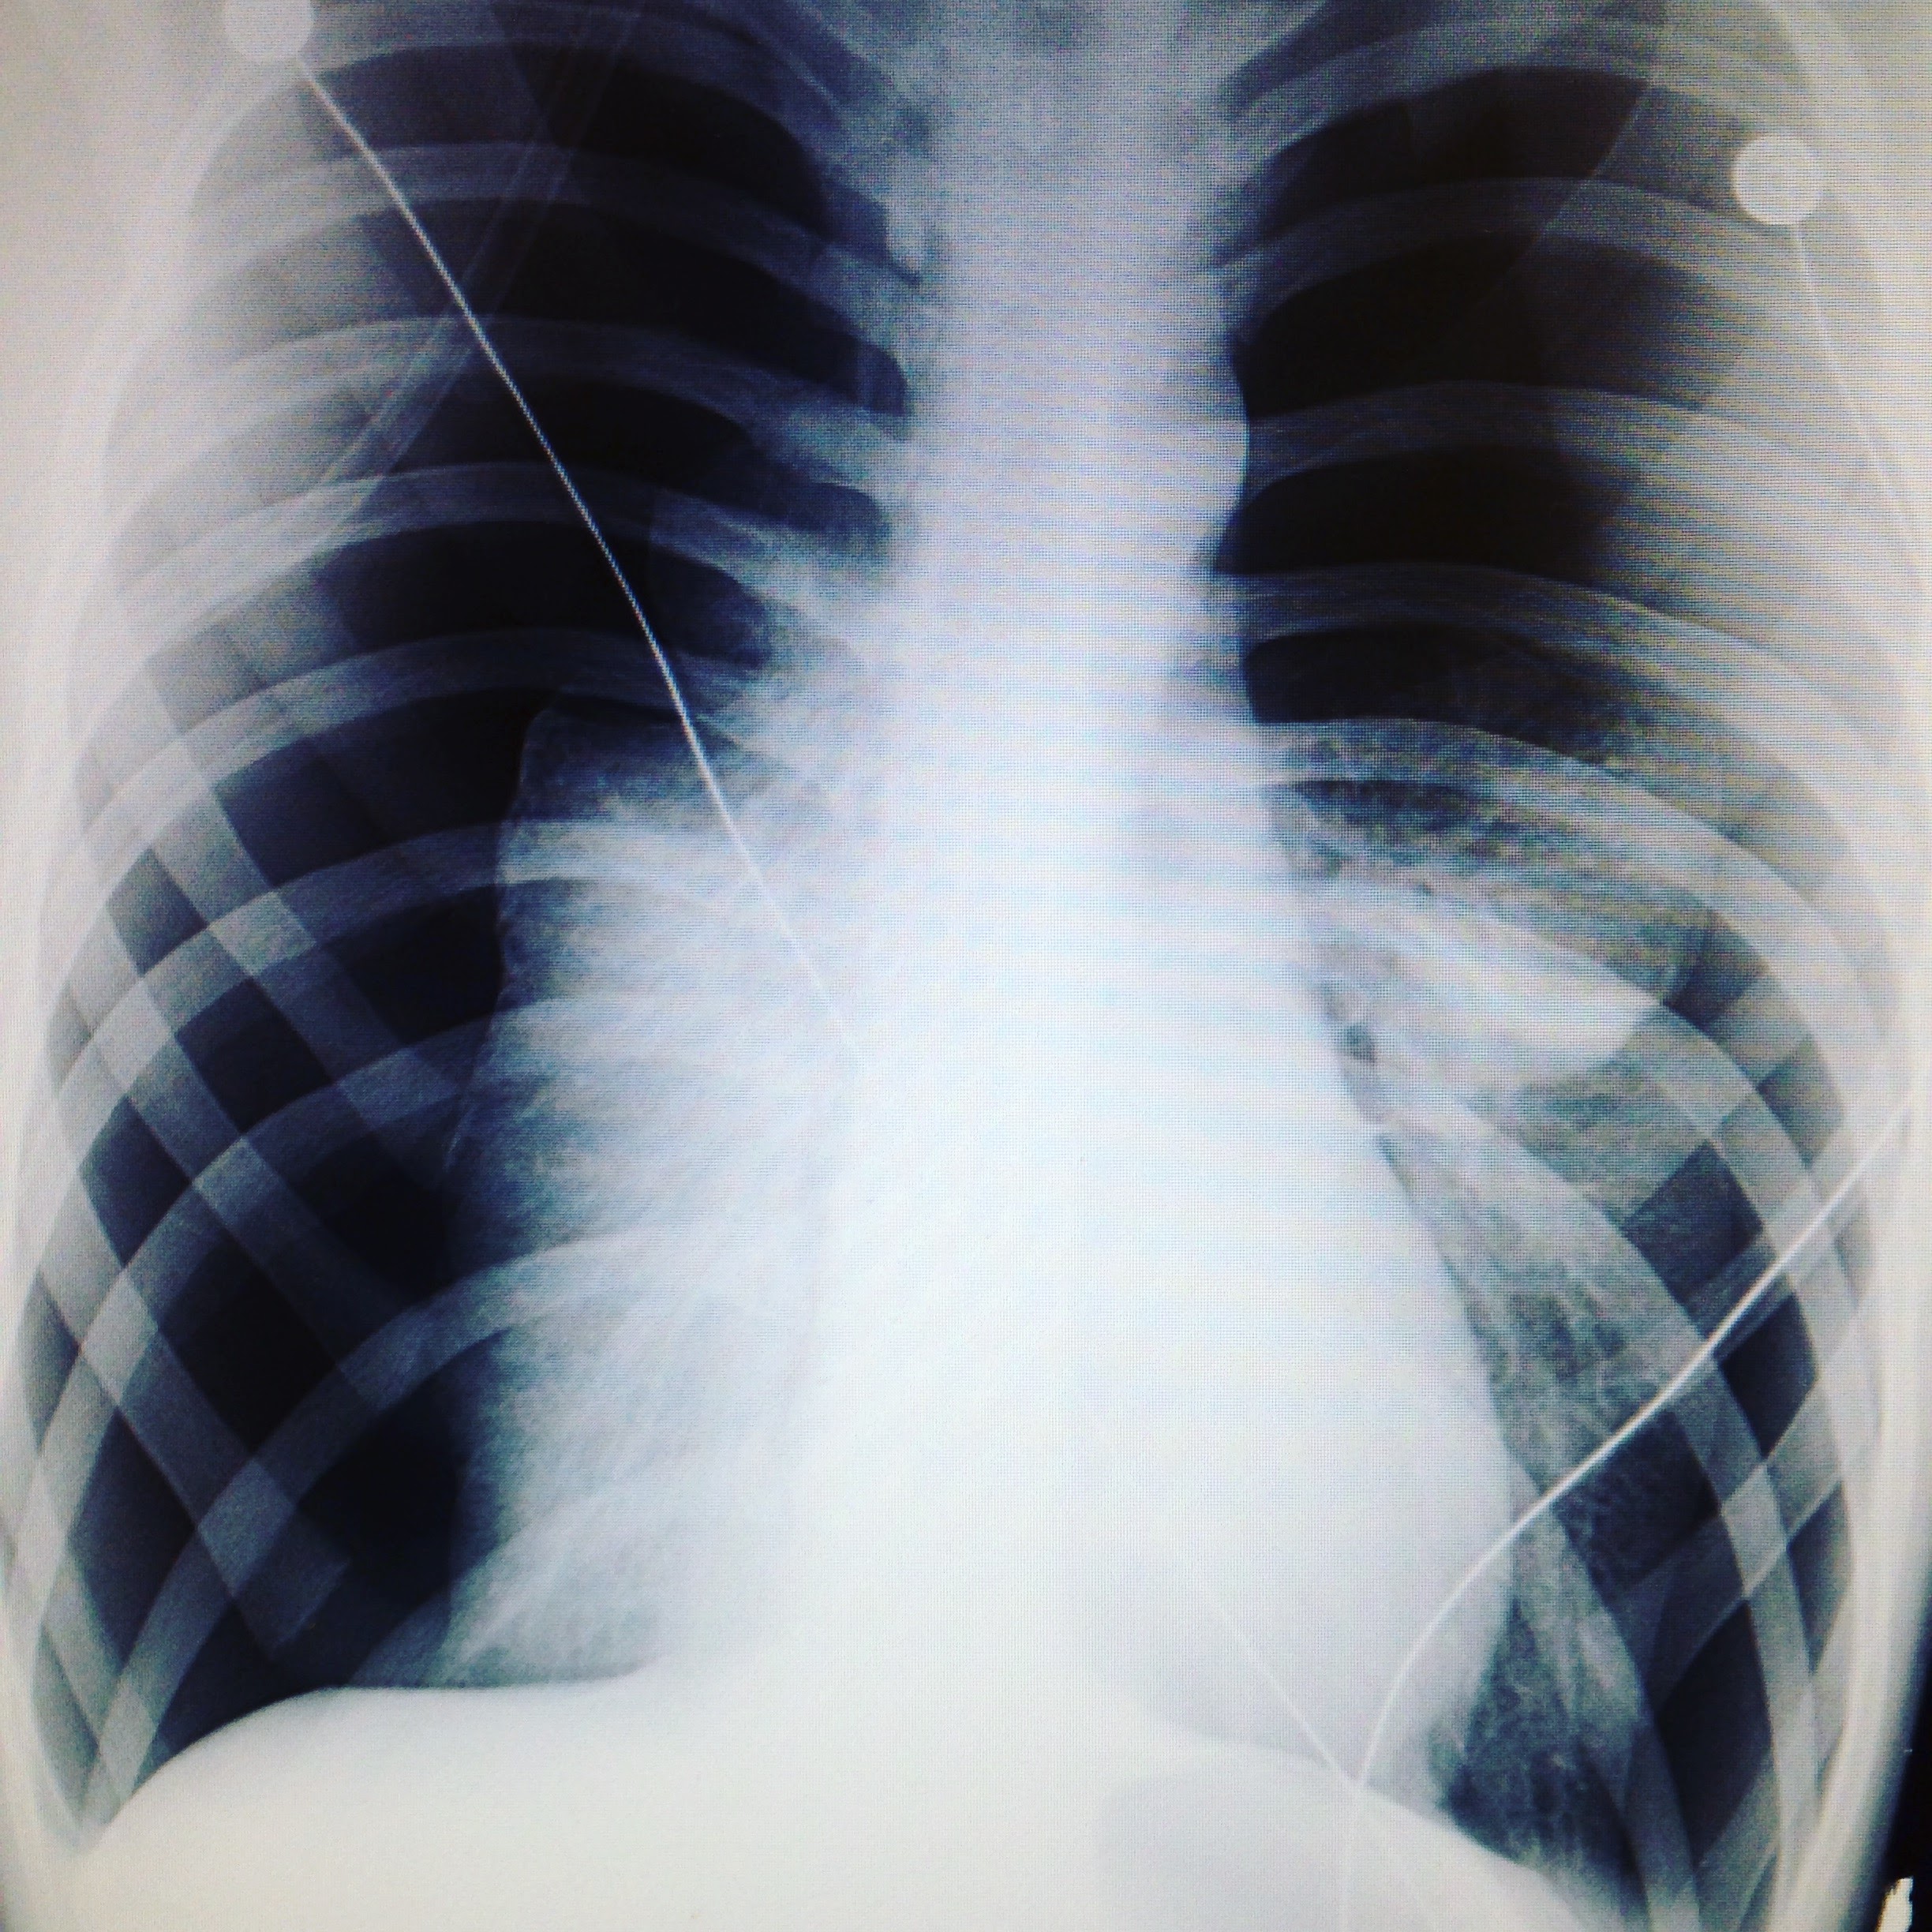

This is an x-ray of my chest that day.

Both my lungs collapsed to a very dangerous level - the small white parts either side of my spine are my lungs, the black space in the rest of the image is the pneumothorax.